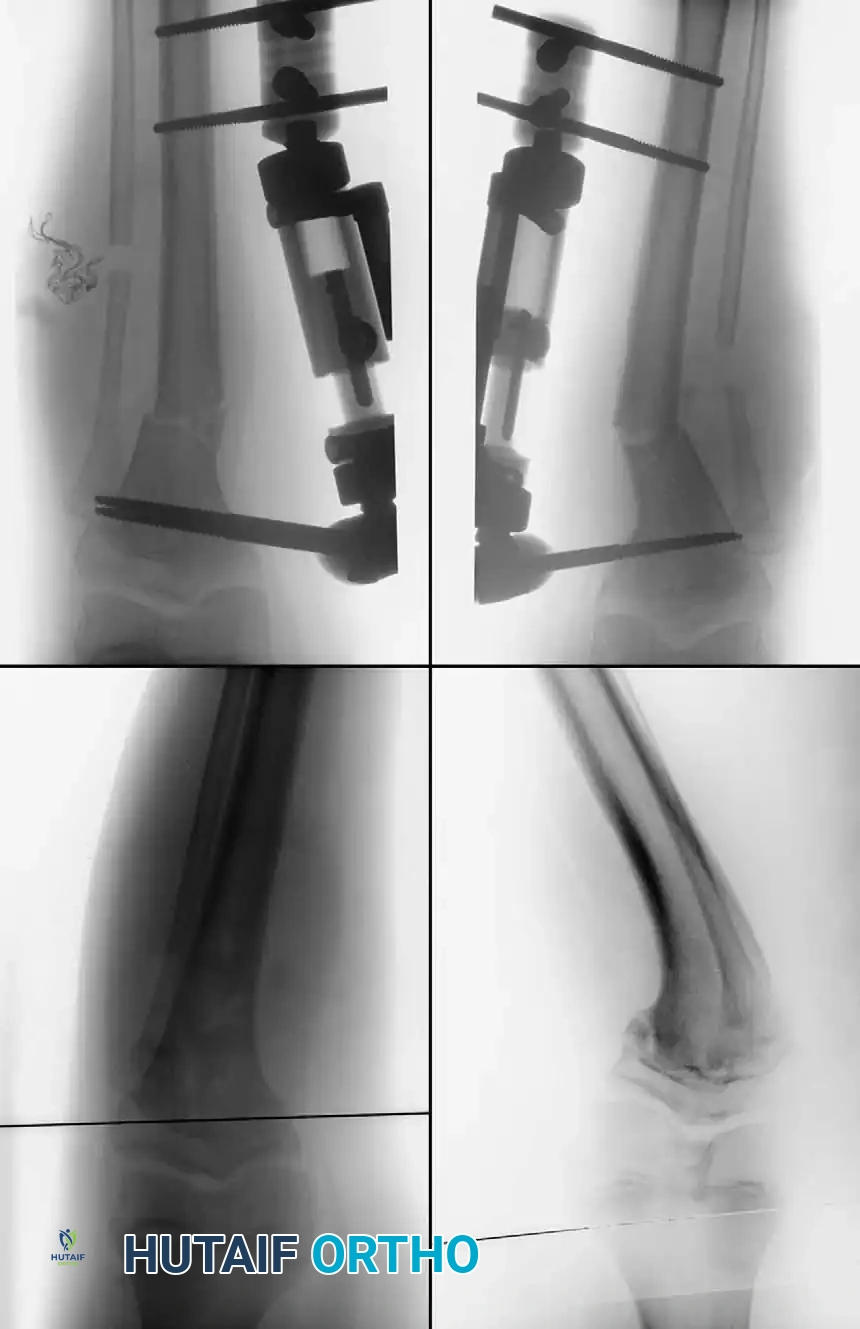

- Fixation: Fixation depends on surgeon preference and patient age. Options include crossed Kirschner wires incorporated into a long-leg cast, rigid internal fixation (plates and screws), or external fixation (Ilizarov or Taylor Spatial Frame), which allows for gradual postoperative correction.

* External Fixation: Pin site care is paramount. Gradual correction protocols begin 7-10 days postoperatively. Weight-bearing is often permitted as tolerated to stimulate bone healing.

- Alekberov C, Shevtsov VI, Karatosun V, et al: Treatment of tibia vara by the Ilizarov method, Clin Orthop Relat Res 409:199, 2003.

- Feldman DS, Madan SS, Koval KK, et al: Correction of tibia vara with six-axis deformity analysis and the Taylor spatial frame, J Pediatr Orthop 23:387, 2003.